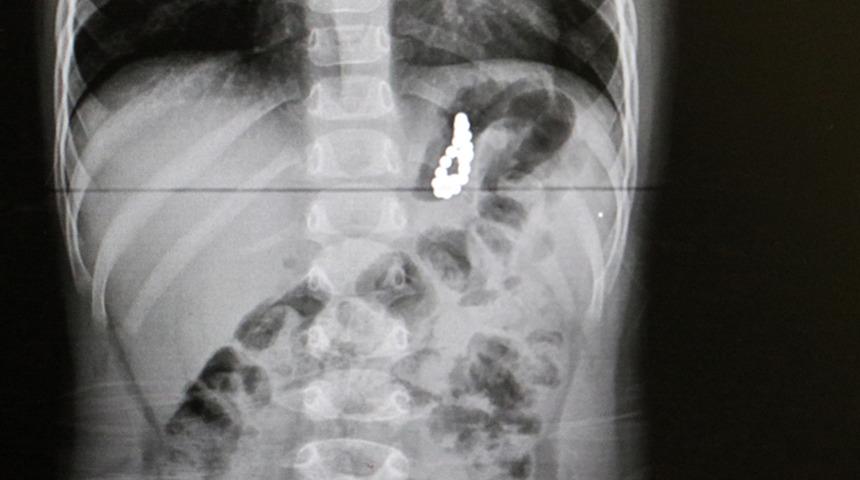

Pamukkale ilçesinde yaşayan Özdemir ailesinin 19 aylık çocukları Murat, geçen hafta aniden rahatsızlanınca özel bir hastaneye götürüldü. Akciğer enfeksiyonu şikayeti üzerine çekilen röntgende, çocuğun midesinde yabancı cisim bulunduğu tespit edildi.

Pamukkale Üniversitesi Hastanesine götürülen çocuk için burada acil ameliyat kararı alındı. Çocuk Gastroenteroloji Öğretim Üyesi Doç. Dr. Halil Kocamaz ve ekibi, Murat'ın midesindeki 5 milimetre çapındaki 17 boncuk mıknatısı yaklaşık 2 saat süren operasyonla çıkardı.

Midedeki boncuk şeklindeki mıknatısların bir arada toplanması, röntgen ve endoskopi görüntüsüne de yansıdı. Operasyonun ardından normal servise alınan Murat Özdemir'in tedavisi sürüyor.